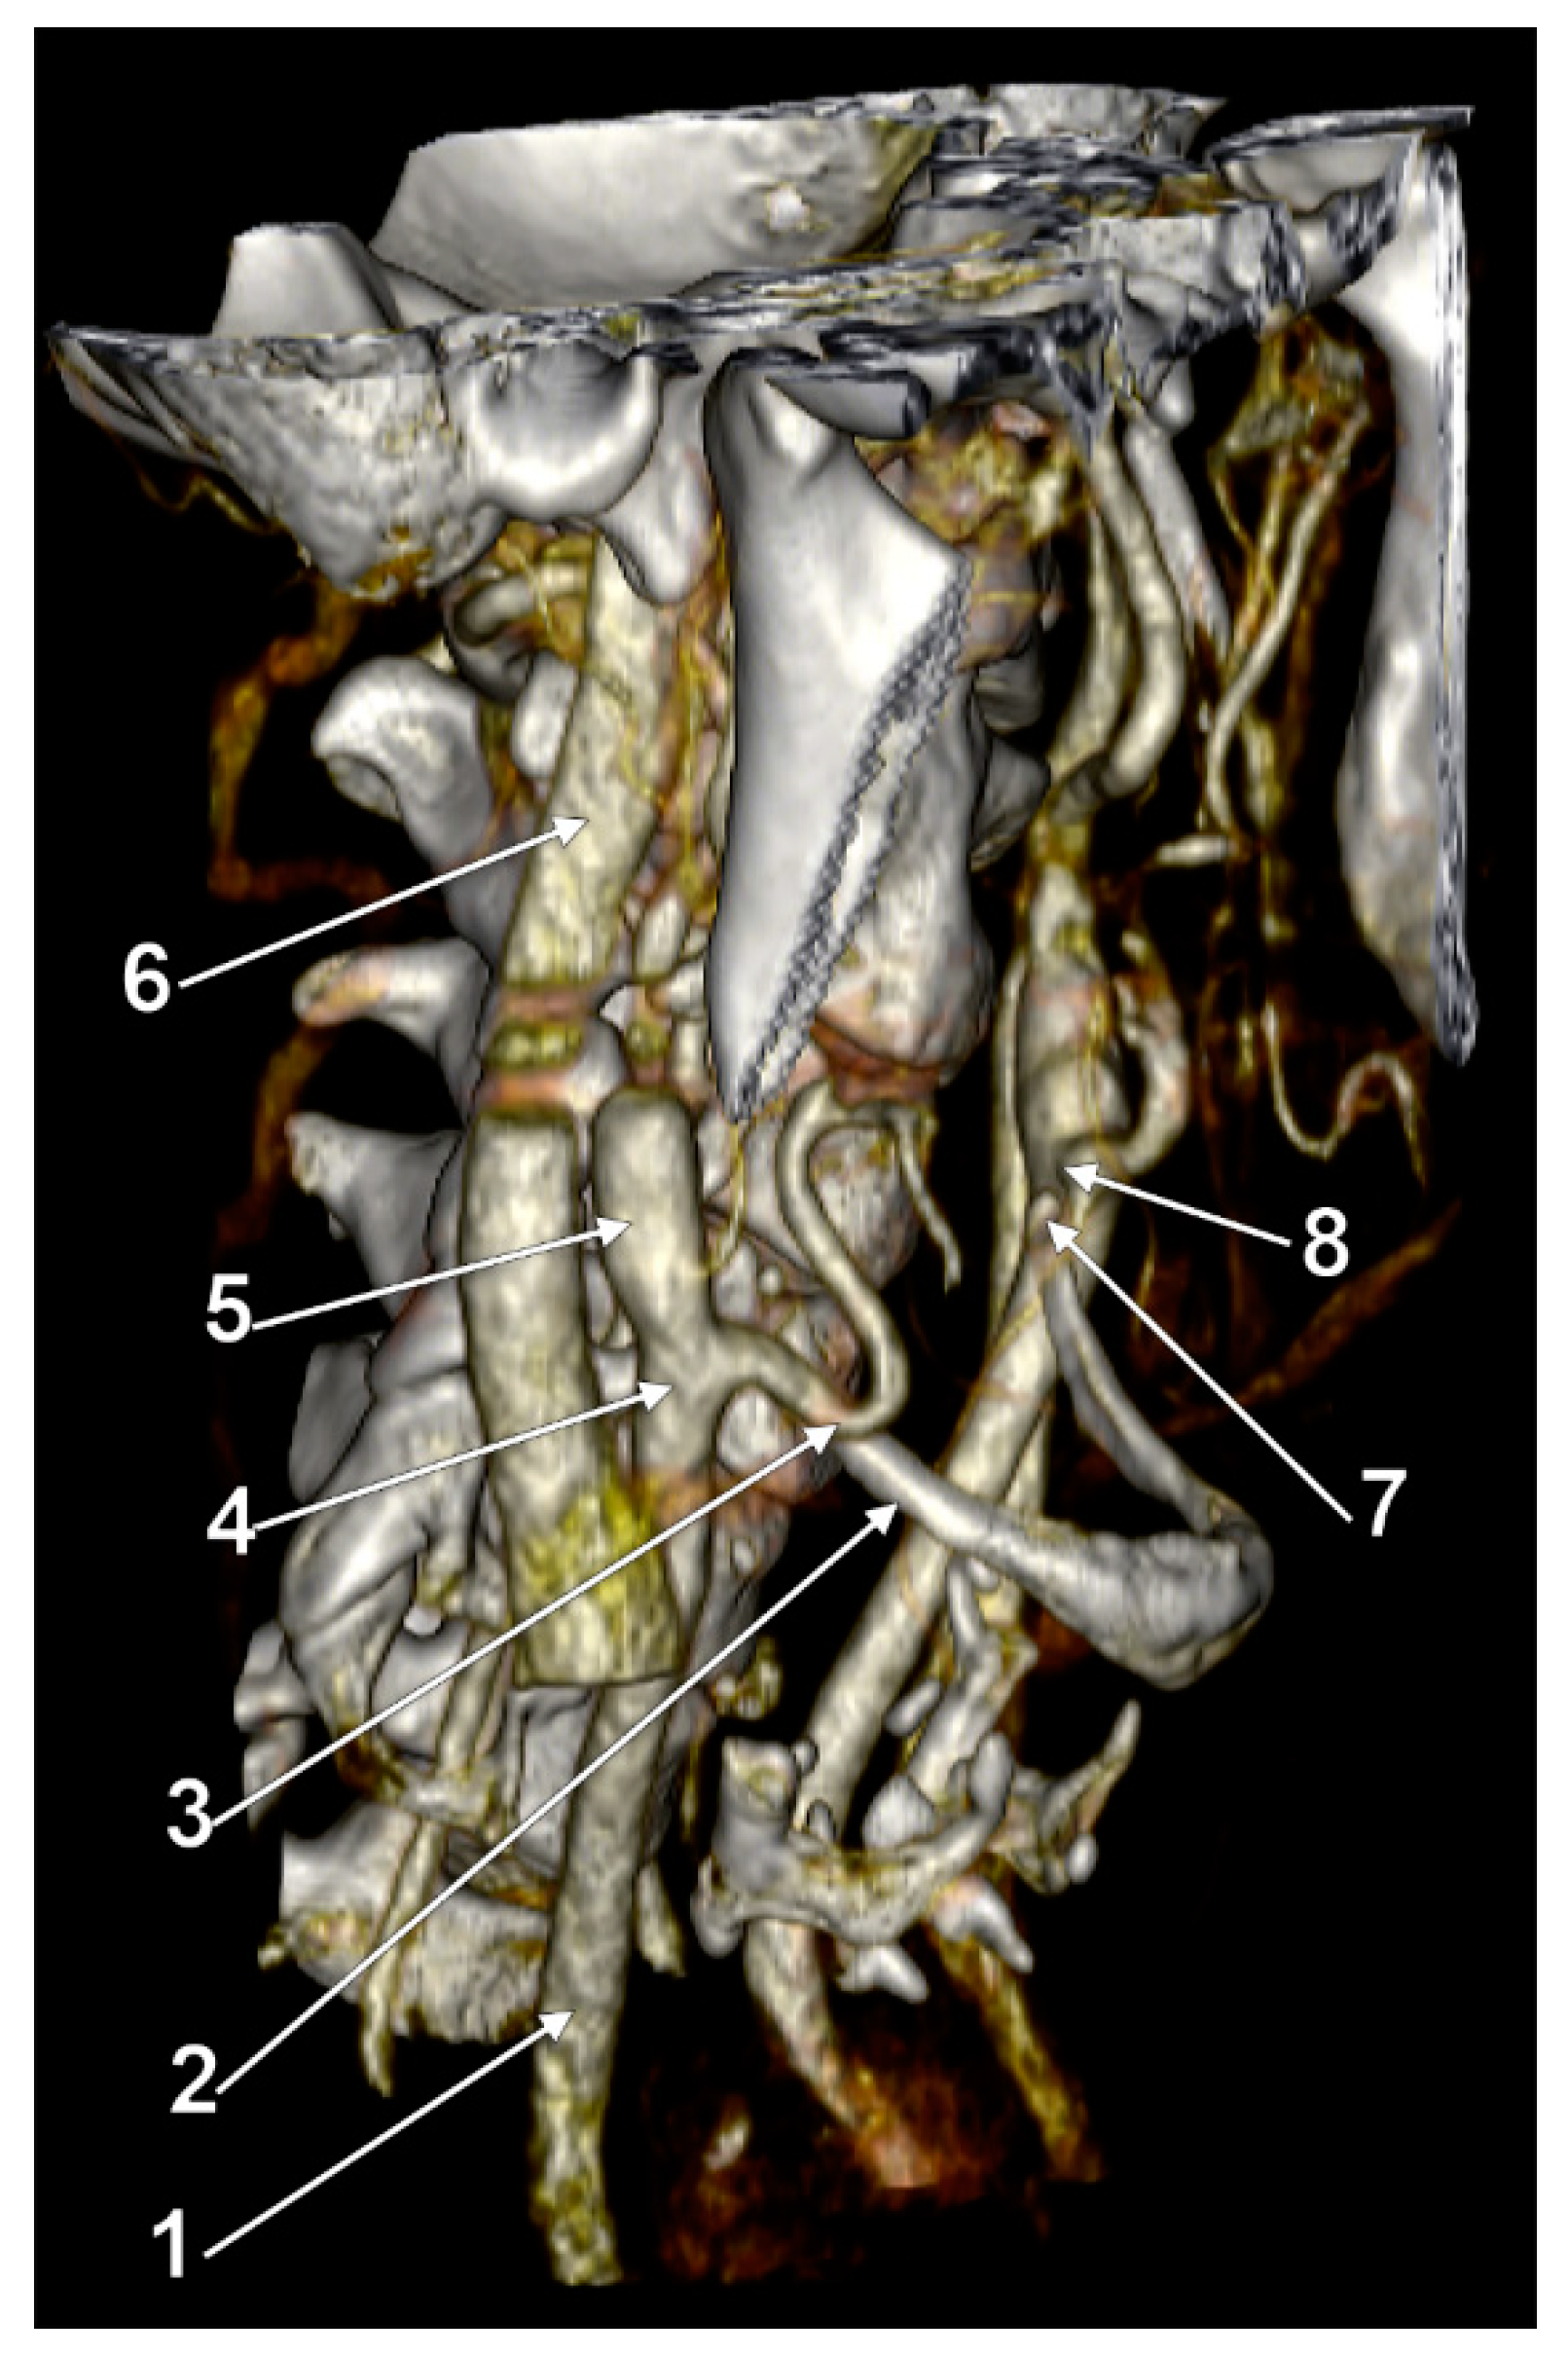

3. Results